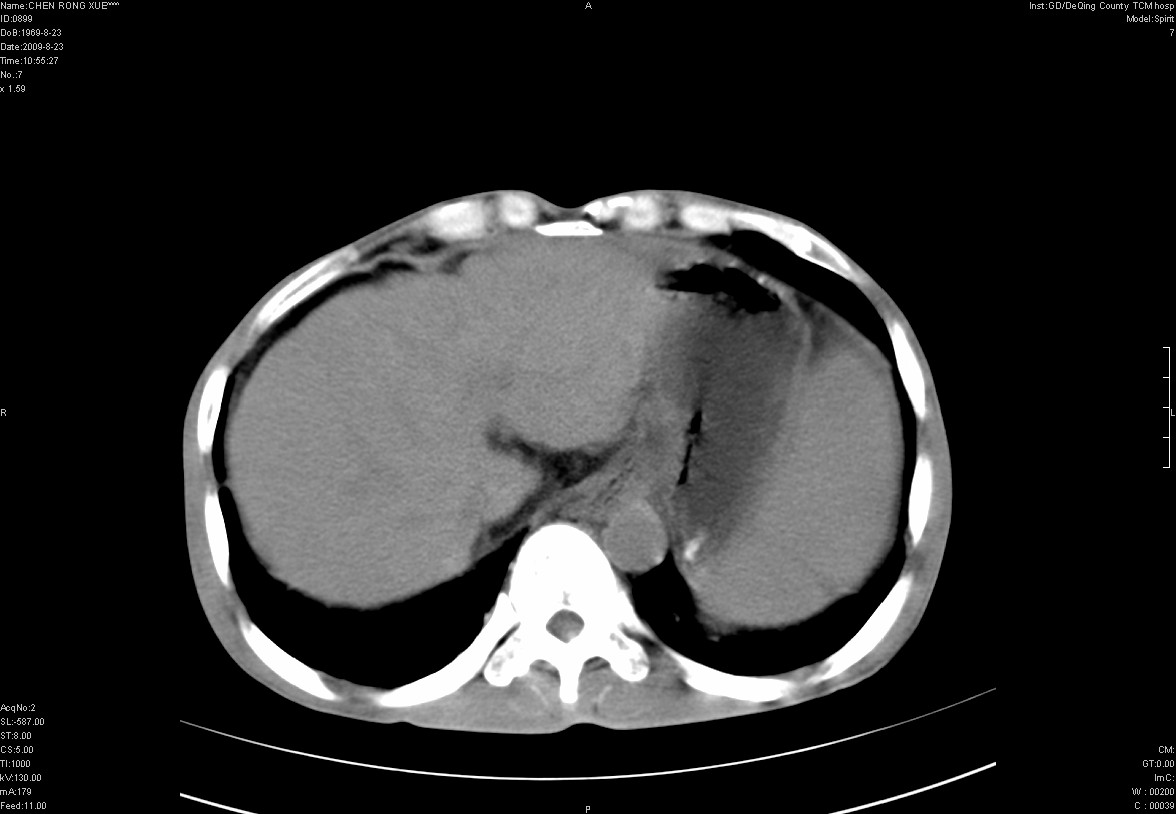

以下是引用zxl51642在2009-8-23 12:56:00的发言:[br]1、肝硬化、脾大;2、慢性胆囊炎;3、右肾占位并右侧腰大肌受侵,考虑恶性可能性大,建议增强扫描进一步检查。

以下是引用qiuleiyu在2009-8-23 15:17:00的发言:[br]1、慢性肝病,肝硬化,脾大,门脉高压。胆囊小结石。[br]2、右肾明显肿大,伴片状低密度灶,累及右侧腰大肌,肿瘤及炎症性病变皆有可能大,建议增强。

以下是引用zjzjr在2009-8-23 17:42:00的发言:[br]1、慢性肝病,肝硬化,脾大,门脉高压。胆囊小结石。[br]右肾脓肿波及肾周,建议增强

以下是引用dyqct在2009-8-23 16:53:00的发言:[br][quote]以下是引用qiuleiyu在2009-8-23 15:17:00的发言:[br]1、慢性肝病,肝硬化,脾大,门脉高压。胆囊小结石。[br]2、右肾明显肿大,伴片状低密度灶,累及右侧腰大肌,炎症性病变可能,建议增强。